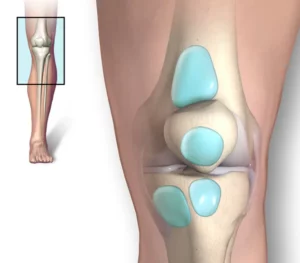

Knee bursitis

Knee bursitis is a condition in which one or more small fluid-filled sacs near the knee joint become inflamed. The sacs are called bursae. Bursae reduce friction and cushion pressure points between bones and tendons, muscles and skin near the joints.